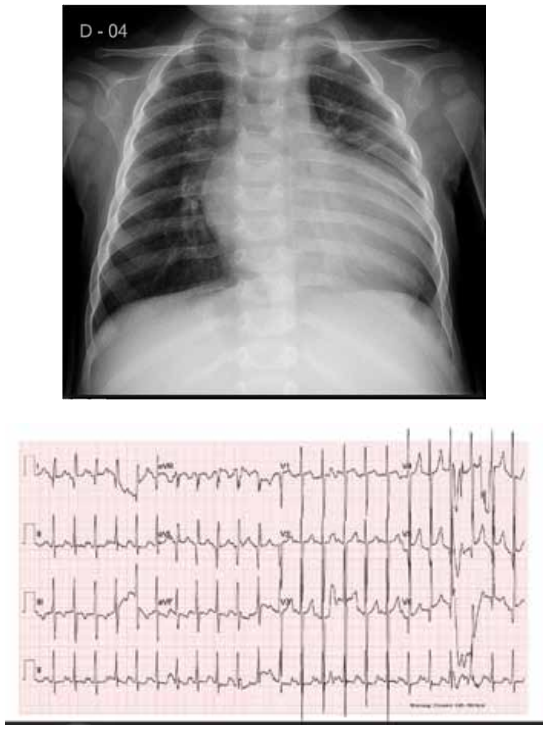

Mãe de paciente de 4 anos refere que sua filha recebeu

diagnóstico de cardiopatia congênita com 2 anos de vida

por ocasião de internação por bronquiolite e que foi introduzido o uso de furosemida. Refere, ainda, que a criança

sempre apresentou pés e mãos roxas aos esforços, cansaço aos esforços médios e bom ganho pondo-estatural.

Ao exame físico da época, evidenciou-se: bom estado

geral; cianose discreta; hidratada; anictérica; hidratada;

eupneica; afebril; baqueteamento digital; frequência cardíaca de 149 batimentos por minuto; saturação de oxigênio ao ar ambiente de 80%; precórdio sem abaulamentos

ou retrações; bulhas rítmicas em 2 tempos e sopro contínuo audível em precórdio e dorso, sobretudo à direita;

pulmões livres; abdome sem visceromegalias. Atualmente, encontra-se com 4 anos de idade, com estabilidade

hemodinâmica. Apresenta, a seguir, radiografia de tórax

e eletrocardiograma.

Qual é a cardiopatia congênita compatível com essa história e com os exames físico e complementar apresentados?